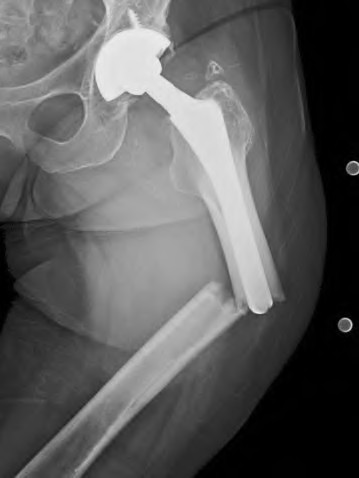

A 67-year-old man who underwent total hip arthroplasty (THA) 4 years ago fell on to his right hip. His pre-injury right hip film is seen in Figure A while films of his current injury are seen in Figures B and C. Prior to the fall he had no thigh or hip pain. His ESR and CRP are within normal limits. During intraoperative assessment, the acetabular and femoral stems are found to be well fixed. What is the next best course of action?

This patient has a periprosthetic hip fracture at the level of the stem with a stable prosthesis, indicated open reduction and internal fixation as the treatment of choice.

The Vancouver Classification can be helpful in clinical decision-making regarding fixation versus revision of periprosthetic hip fractures of the proximal femur. A stable implant, by nature, does not need to be revised in the setting of adequate bone stock for fixation, but the ultimate test of stability should be in the operating room. Many fixation strategies are appropriate, but many implants include locking plate fixation for concerns of stress-shielded bone around the implant as well as use of unicortical fixation at the level of the stem.

Pike et al review the current trends in treating B1 fractures including locking plates with strut allografts, minimally invasive plate osteosynthesis (MIPO) and locking plates spanning femoral THA and TKA stems in selected patients. The authors conclude that no studies currently provide evidence establishing one

Illustration A shows a possible fixation construct for this patient's fracture. The Vancouver Classification is seen in Illustration B and Illustration C represents an algorithm for treatment options.